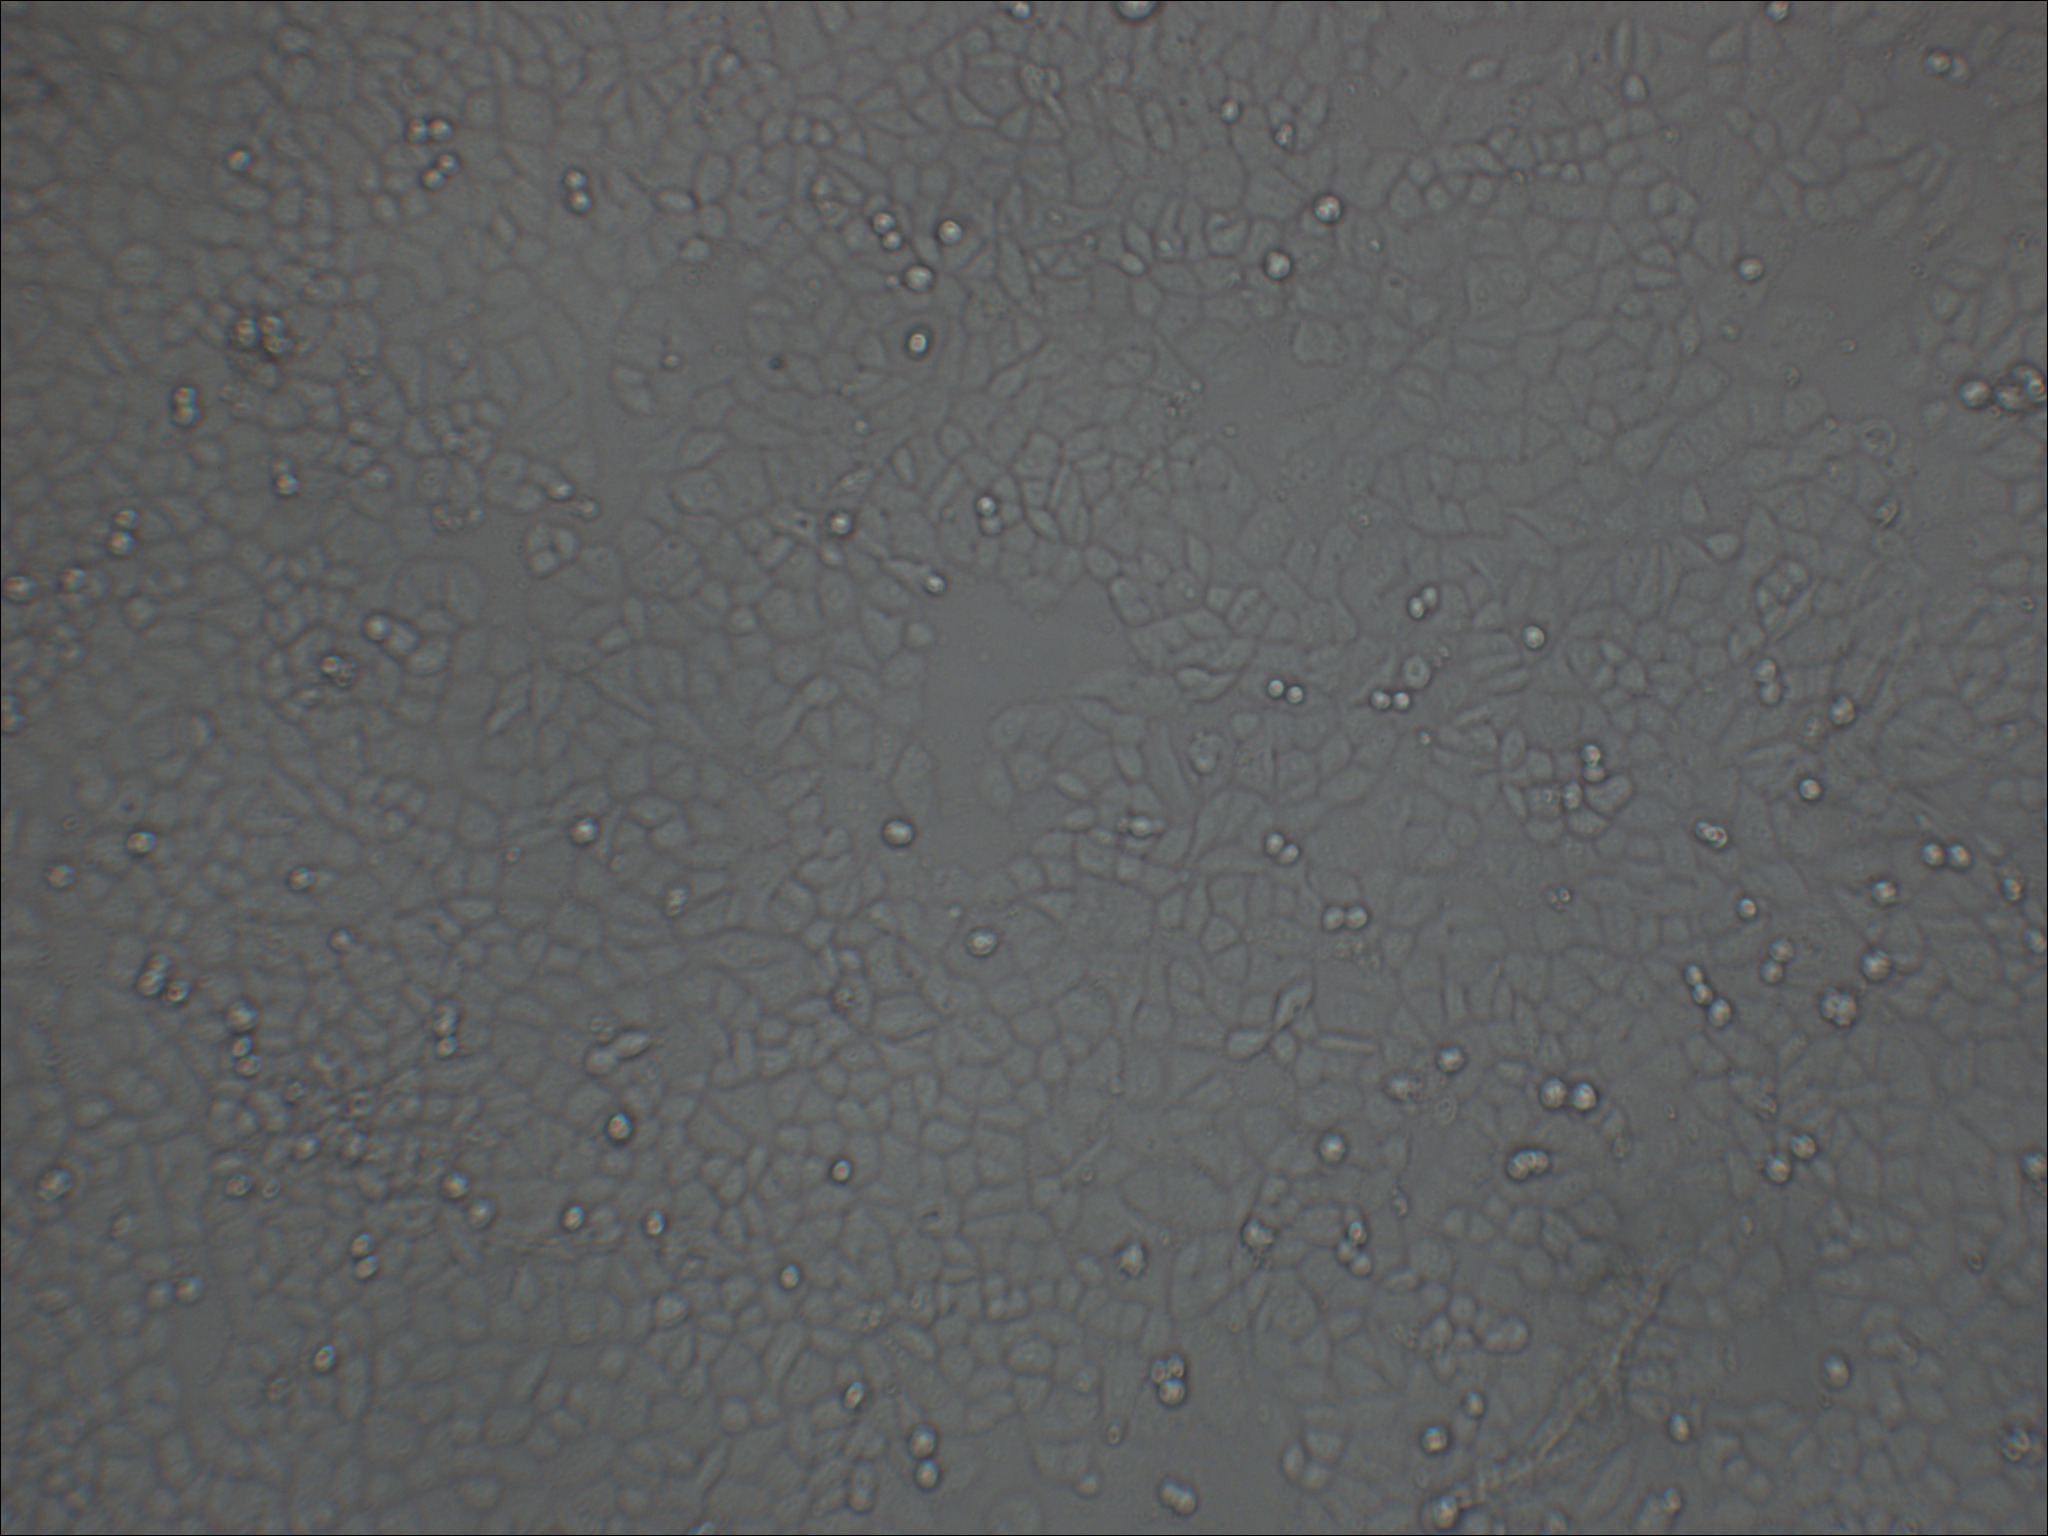

形态特征 上皮细胞样

生长特征 贴壁